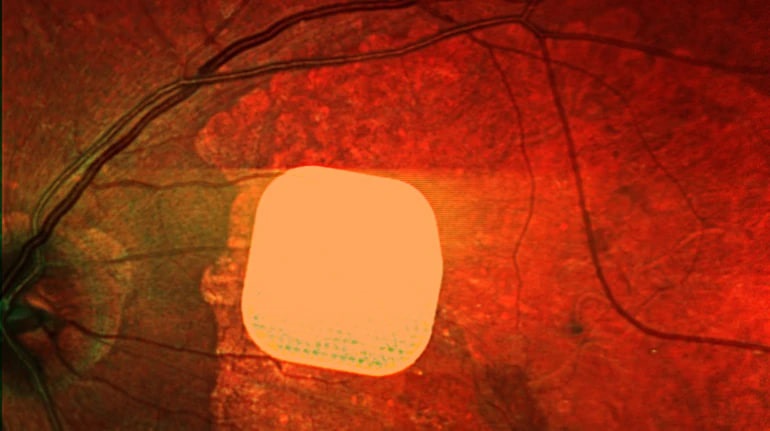

Британські лікарі успішно випробували новий електронний імплант з назвою Prima, який допомагає частково відновити зір людям із віковою сліпотою. Цей мікрочип встановлюють під сітківку ока пацієнтів під час спеціальної операції. Після адаптації до імпланту, 84% учасників дослідження змогли розрізняти літери, цифри та слова, які раніше не могли бачити через втрату центрального зору. Лікарі підкреслюють, що цей імплант відкриває нові можливості для людей із важкими зоровими порушеннями, допомагаючи покращити їхню якість життя та незалежність.